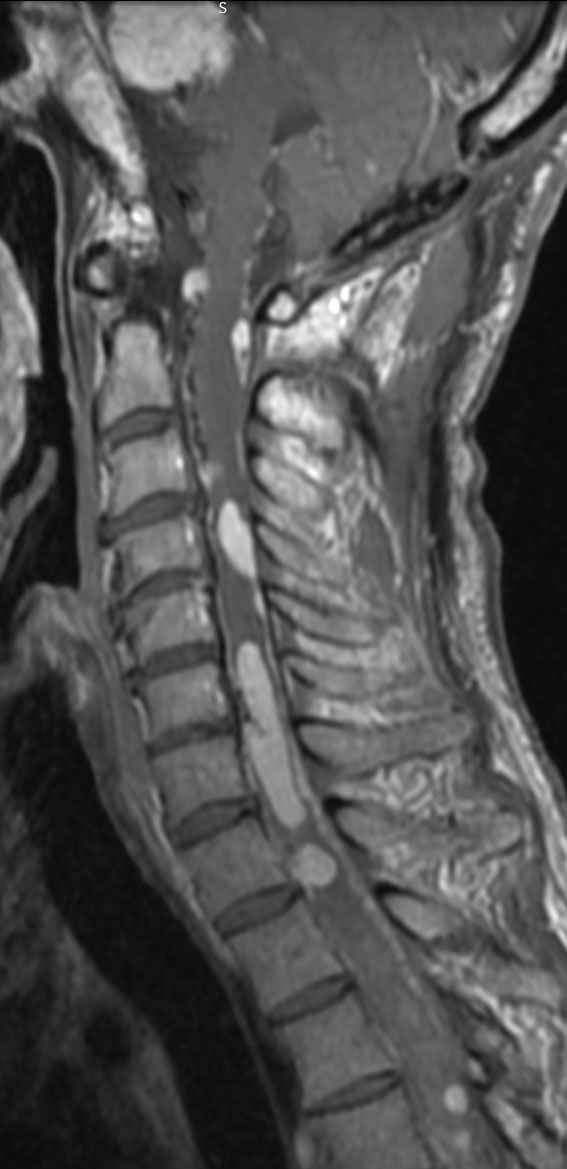

左右の写真は異なった患者さんのものです。両者ともに,大きな嚢胞(水たまり)を伴う小脳内部の小さな血管芽腫です。右の方に小さく白い塊(黄色の矢印)が見えるのですが,それだけが腫瘍で,濃い灰色に見える部分はのう胞といって液体がたまっているだけです。

これはとても(といっては何ですが比較的に)簡単な手術例です。小脳失調によるふらつきや水頭症よる頭痛と嘔吐などを出しますが,手術後に症状は改善します。

一般に小脳半球という場所にできたものは大きくても手術の成功率はとても高いです。小さいものでは場所と症状によってはガンマナイフなどの放射線治療も有効なことがあります。しかし,手術で摘出できるものは摘出した方が確実に治ります。